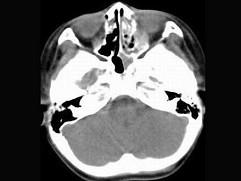

男,7岁,无意发现鼻腔肿物,无明显症状,CT如图所示,最可能诊断为 ( )

• A.鼻炎鼻息肉

答案: A